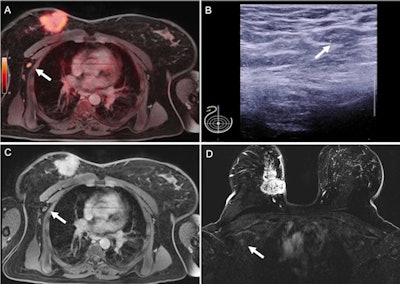

FDG-PET/MRI combined with ultrasound could reduce the need for invasive biopsy to confirm suspicious findings in women with newly diagnosed metastatic breast cancer, according to a study by German researchers published May 20 in the Journal of Nuclear Medicine.

The study found that FDG-PET/MRI outperformed sonography, breast MRI, and thoracic MRI for the detection of axillary lymph node metastases, as well as that FDG-PET/MRI when combined with ultrasound may achieve a level of accuracy that could obviate the need for invasive biopsies.

In this prospective, multicenter study, the researchers conducted a head-to-head analysis of hybrid FDG-PET/MRI imaging and sonography, breast MRI, and thoracic MRI for the detection of axillary lymph node metastases in 112 women with newly diagnosed, therapy-naive breast cancer. Patients (mean age, 53.04 ± 12.6 years) were diagnosed between March 2018 and December 2019.

Thoracic PET/MRI showed the highest ROC-AUC with a value of 0.892. The AUC for breast MRI was 0.782; thoracal MRI was 0.814; and sonography was 0.834. Differences between the modalities were statistically significant. PET/MRI also showed the highest sensitivity (81.8%, 36/44), while axillary sonography had the highest specificity (98.5%, 65/66).

"In our study, [F-18] FDG PET/MRI demonstrated the best diagnostic performance in detecting nodal positive patients compared to the other modalities," the researchers stated.

Given that ultrasound had the highest specificity, the authors suggested future workflows should consider performing FDG-PET/MRI as a "searching tool" before clip-marking of the primary tumor, if applicable in clinical workflow, and then adding axillary sonography to specify findings.